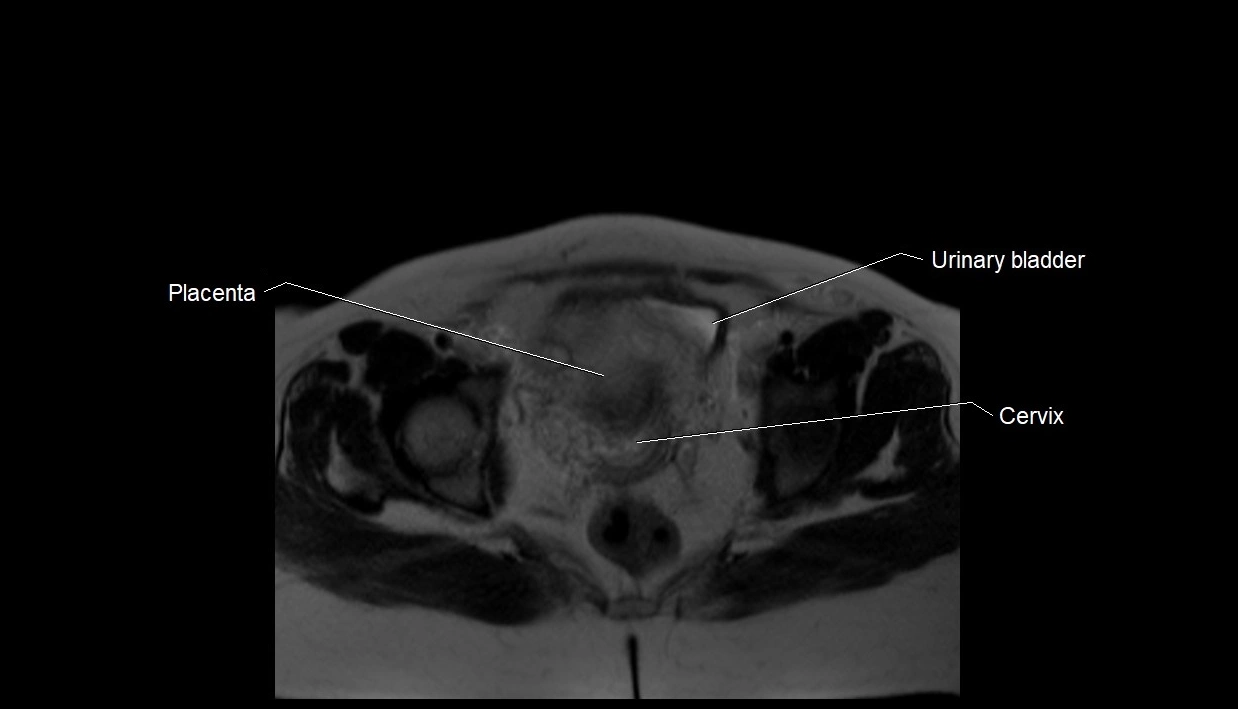

MRI Appearance

T2 HASTE (T2 GRE):

• Amniotic fluid shows very bright hyperintense signal

• Provides natural contrast against fetus and placenta

• Small particles (vernix) may appear as scattered hypointense foci within bright fluid

T1 GRE:

• Amniotic fluid shows low signal intensity (dark)

• Hemorrhage, infection, or proteinaceous content may cause focal or diffuse high signal intensity

MRI image

image